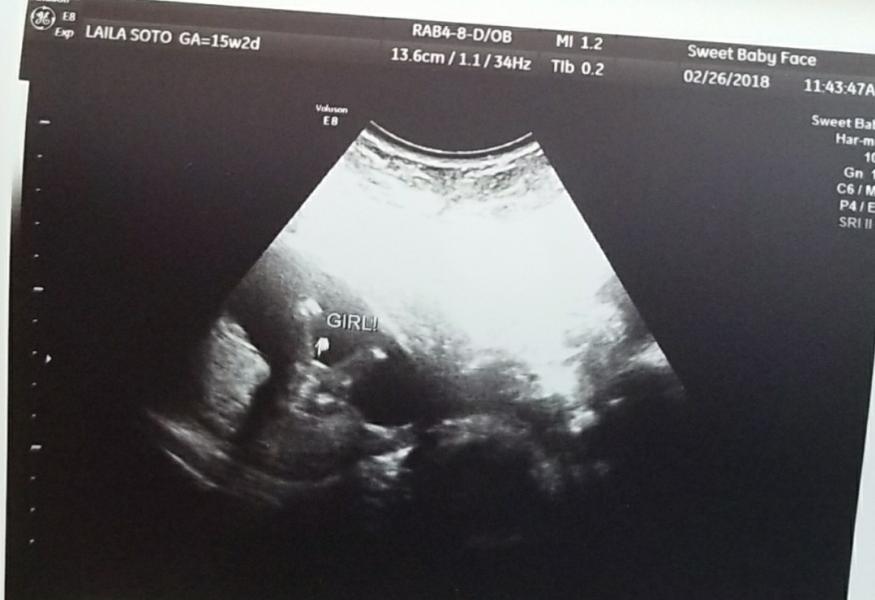

I was told girl at 15 weeks scan,what do you ladies think?

@laila92 nope that's for sure agirl that's exactly how my daughter's us looked ,congrats mommy

@laila92, but it’s still very early to tell.

I think girls are supposed to have three even lines arnt they @amberspringer ?

I don’t know cause my girls always had 3 lines there lol.

She's indeed a girl. Was confirmed on Thursday 😁😍💖